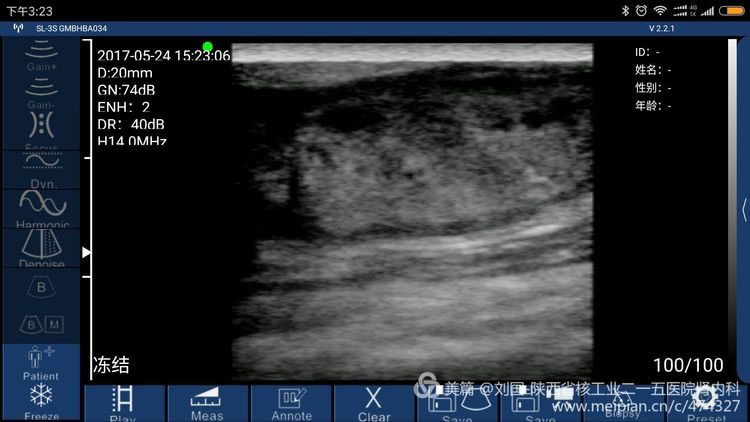

The patient’s barchial artery was punctured in error by a nurse of some hospital’s blood purification center, which caused large area of his arm was bruising and his arm swells, covering up doctors and nurses’ awareness, not to find out mistaken puncture timely and barchial artery’s crevasse, and not to timely oppress the barchial artery effectively. Till the bruising was totally dispersed, the swell faded away, part of the below gradually enlarged to impact the forearm buckling. After he saw a doctor in our hospital, I found I could heard hemokinesis sound. Pseudoaneurysm of elbow brachial artery with 3mm-crevasse was confirmed by ultrasound.

Result checked by Sonostar’s wireless ultrasound, and displayed by my mobile phone-Mi max

Sonostar’s True Features